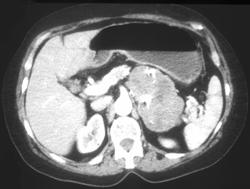

Gastric Adenocarcinoma